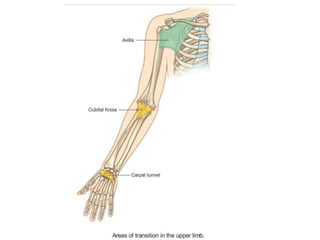

TRANSITION AREAS OF UPPER LIMB

• Axilla

• Cubital fossa

• Carpal tunnel

• Important structures pass through, or are related

to, each of these areas